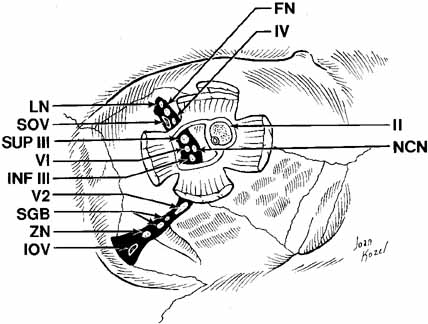

The orbital apex contains a plethora of vital structures. A large number

of arteries, veins, and nerves pass through several significant foramina. The

superior orbital fissure is a transverse notch between the greater

and lesser wings of the sphenoid bone that descends medially (see Fig. 1). Although the shape of the superior orbital fissure is variable, the

superior portion is usually narrower where the lacrimal, frontal, and

trochlear nerves pass (Fig. 6). The middle meningeal artery anastomosis with the ophthalmic artery

may enter here, if not through its own foramen, more anteriorly in

the roof. Most of the venous drainage from the orbit and the globe flow

through the superior orbital fissure to the cavernous sinus. Other

structures passing through the superior orbital fissure within the annulus

of Zinn include the superior and inferior divisions of the third

cranial nerve, the sixth cranial nerve, and the nasociliary branch of

the ophthalmic trigeminal nerve (Fig. 6). Fig. 6 Orbital apex with nerves coursing through foramina. (LN, lacrimal nerve; NCN, nasociliary nerve; FN, frontal nerve; VI, abducens nerve; IV, trochlear nerve; INF III, inferior division of cranial nerve III; SOV, superior ophthalmic vein; II, cranial nerve II; SUP III, superior division of cranial nerve III; IOV, inferior ophthalmic vein; ZN, zygomatic nerve; V2, V2 nerve; SGB, sphenopalatine ganglion branches) Fig. 6 Orbital apex with nerves coursing through foramina. (LN, lacrimal nerve; NCN, nasociliary nerve; FN, frontal nerve; VI, abducens nerve; IV, trochlear nerve; INF III, inferior division of cranial nerve III; SOV, superior ophthalmic vein; II, cranial nerve II; SUP III, superior division of cranial nerve III; IOV, inferior ophthalmic vein; ZN, zygomatic nerve; V2, V2 nerve; SGB, sphenopalatine ganglion branches)